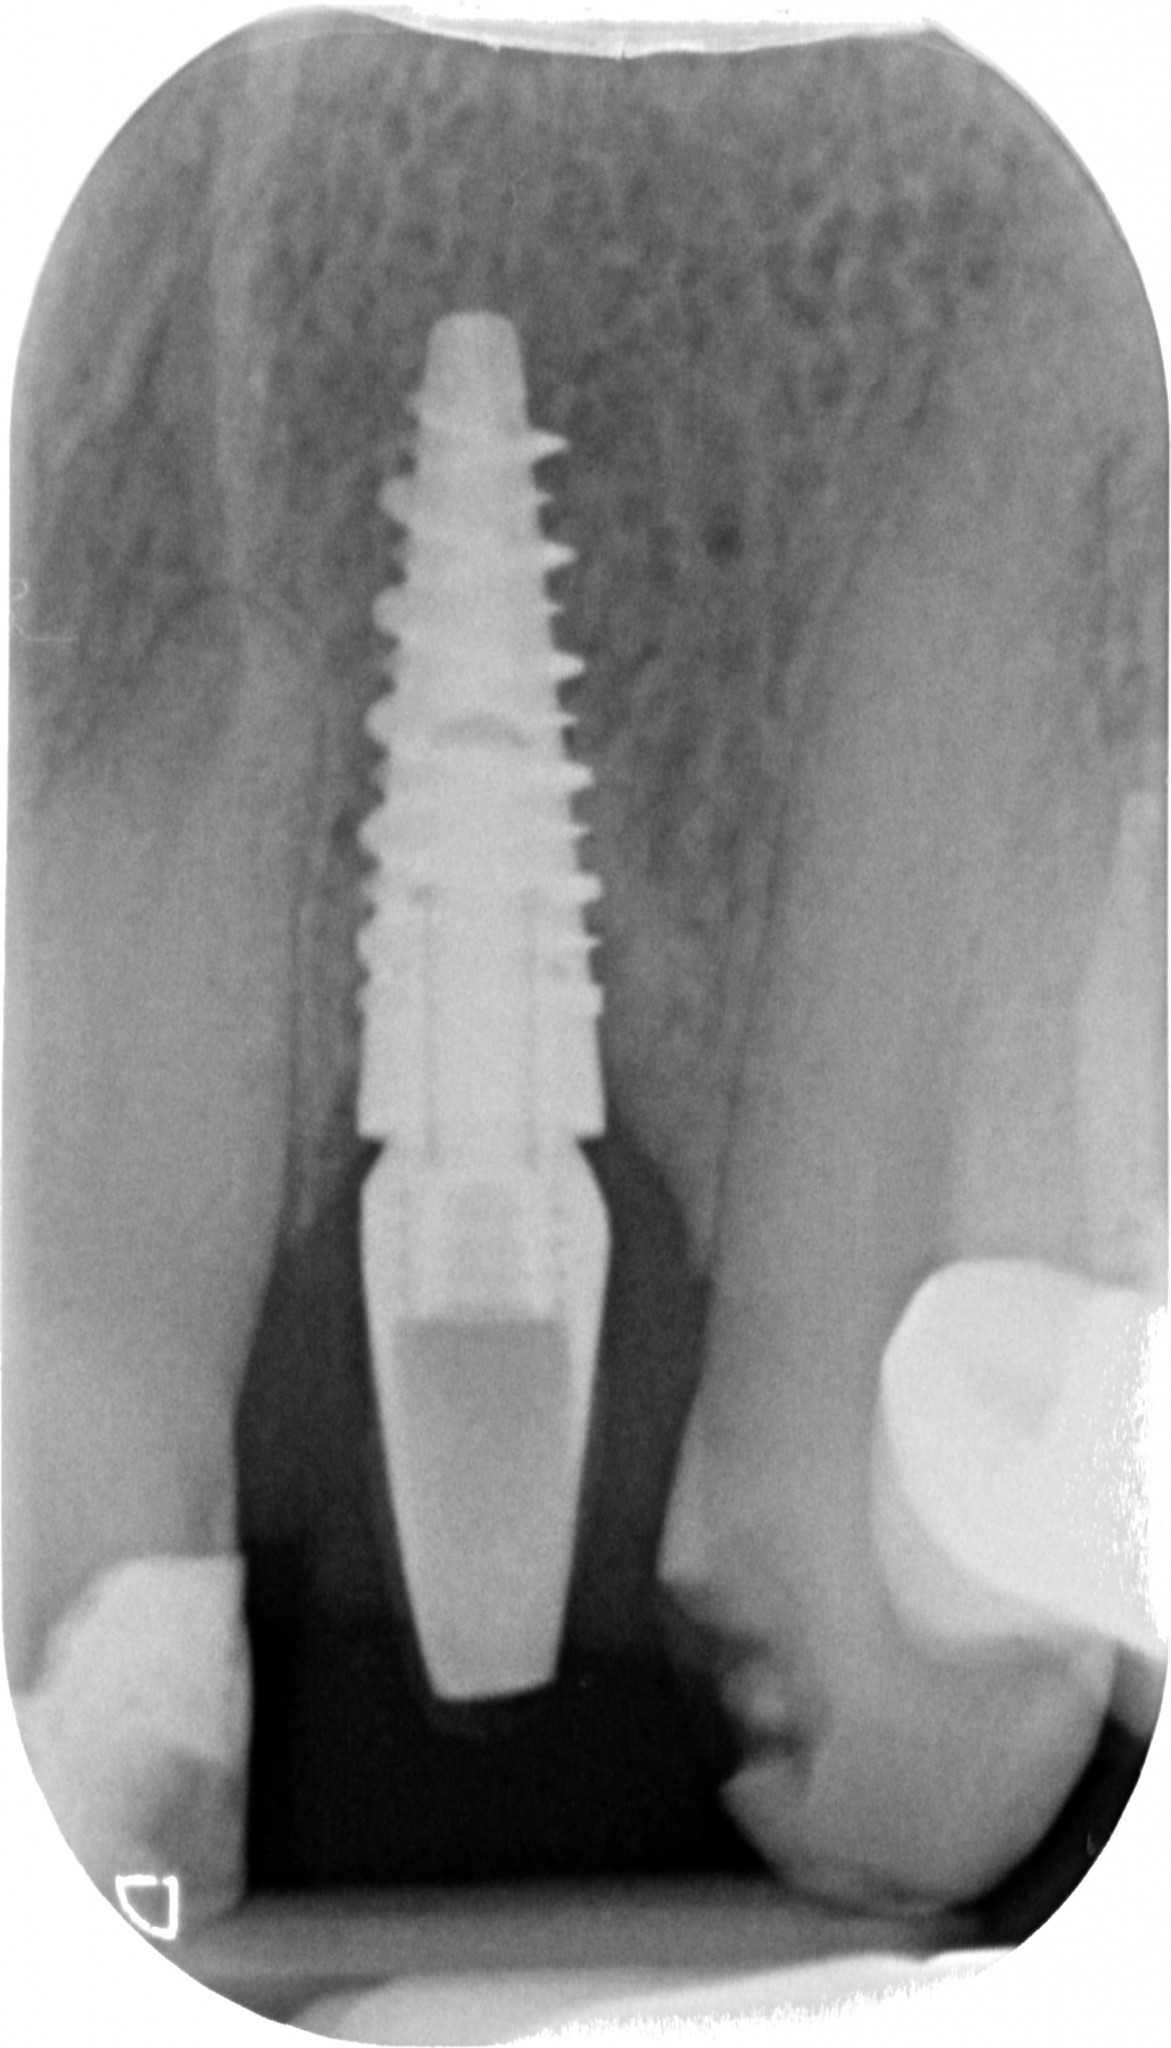

“Guarda questa lastra, cosa ne dici? Sta bene questo impianto?”

gestione dei tessuti molli -rx

PERFETTO direi io, neanche un po’ di riassorbimento. Credo che tu sia d’accordo con me.

La signora Rosetta ha finito questo lavoro dal suo vecchio dentista esattamente 6 mesi fa. Appena messo la corona definitiva ha iniziato a lamentarsi di un fastidio continuo. Il collega, non so in base a quale presupposto teorico, ha rimosso il definitivo e rimesso il provvisorio.

Sintomo invariato, Rosetta continuava ad avere fastidio. Al che il collega, che non ho la più pallida idea di chi sia, ha attuato la TECNICA DELLE TECNICHE… che ho visto impiegare più volte e in molti studi nella mia giovanile carriera di marchettaro: